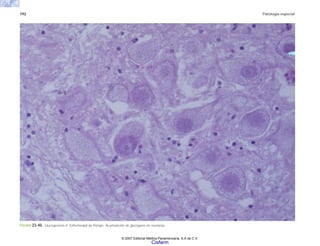

H